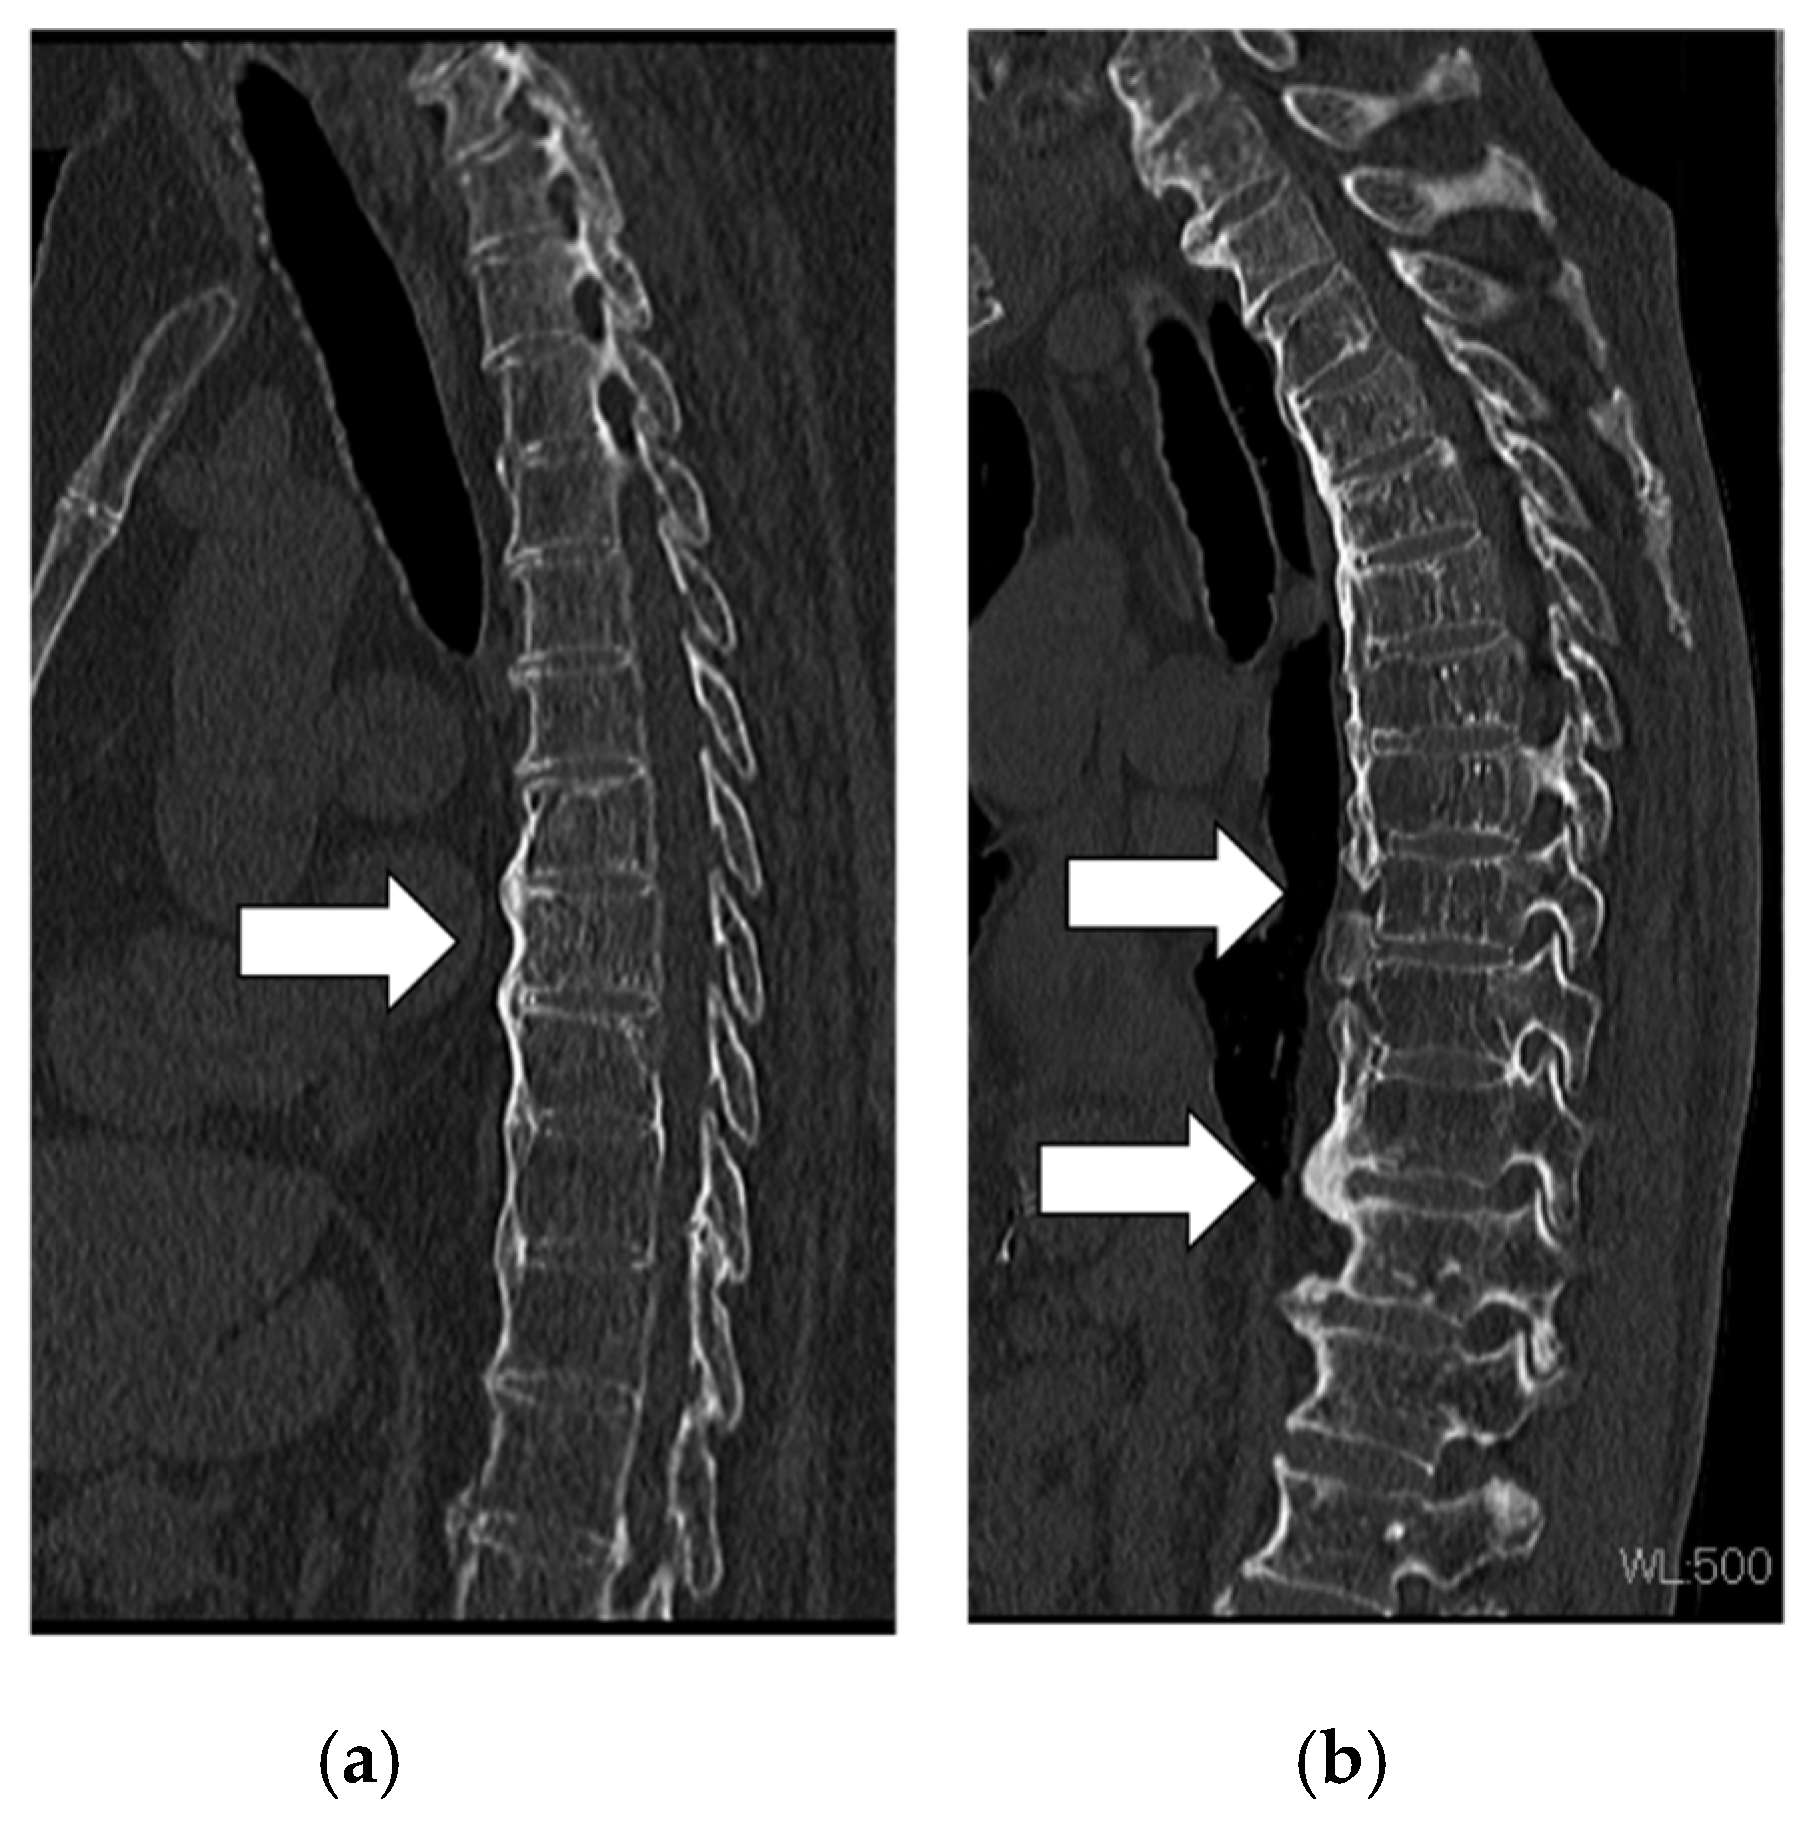

Figure 1.

Actual ossified morphology of diffuse idiopathic skeletal hyperostosis. Images from a patient showing (a) flat ossification and (b) large and discontinuous ossification.